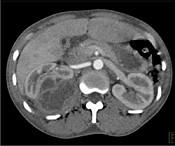

问题 一女性患者,一月前出现尿频、尿急等症状为引起注意,现有高热,阅图后最可能的诊断为 ( )

选项 A.急性肾盂肾炎 B.肾脓肿 C.多囊肾 D.肾结核 E.肾癌

答案 B